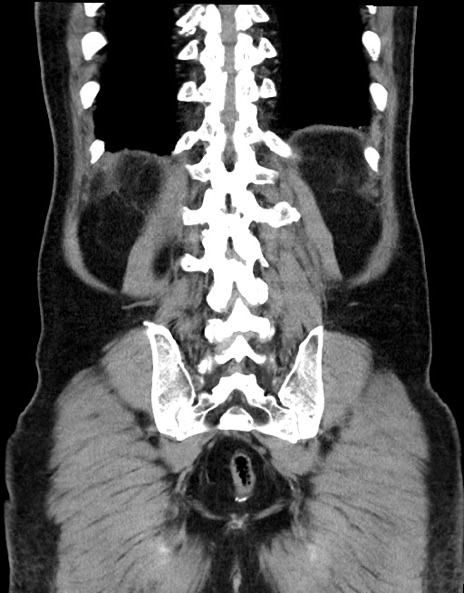

症例15(冠状断像)

【症例】70歳代男性

【主訴】腹痛

【現病歴】今朝から腹痛あり。全体的に痛い。特に左上の方。排ガスが今日はない。冷や汗が出る。

【既往歴】直腸癌術後

【身体所見】左側腹部〜上腹部に圧痛あり。腹膜刺激症状明らかなではない。軽度反跳痛。左下腹部に術後瘢痕あり。

【データ】WBC 7700、CRP 0.02

横断像